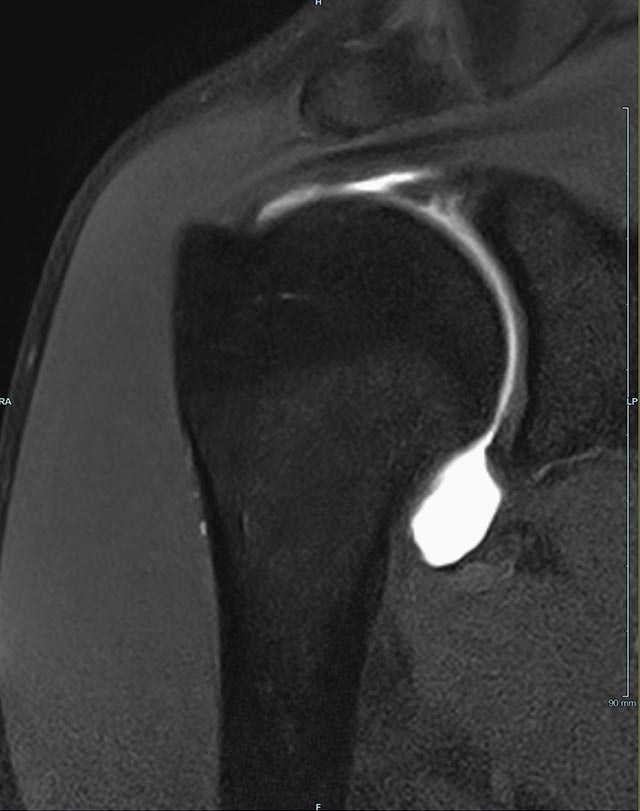

Gelenke

• Beurteilung von Knochen, Bändern und anderen Weichteilstrukturen der Gelenke nach Unfall.

• Arthrosediagnostik (Knorpelschaden)

• Impingement-Symptomatik

• Ursachenklärung bei wiederholter spontaner Gelenkluxation

• Ausbreitungsdiagnostik bei Gelenkentzündung, z.B. im Rahmen von rheumatischen Grunderkrankungen